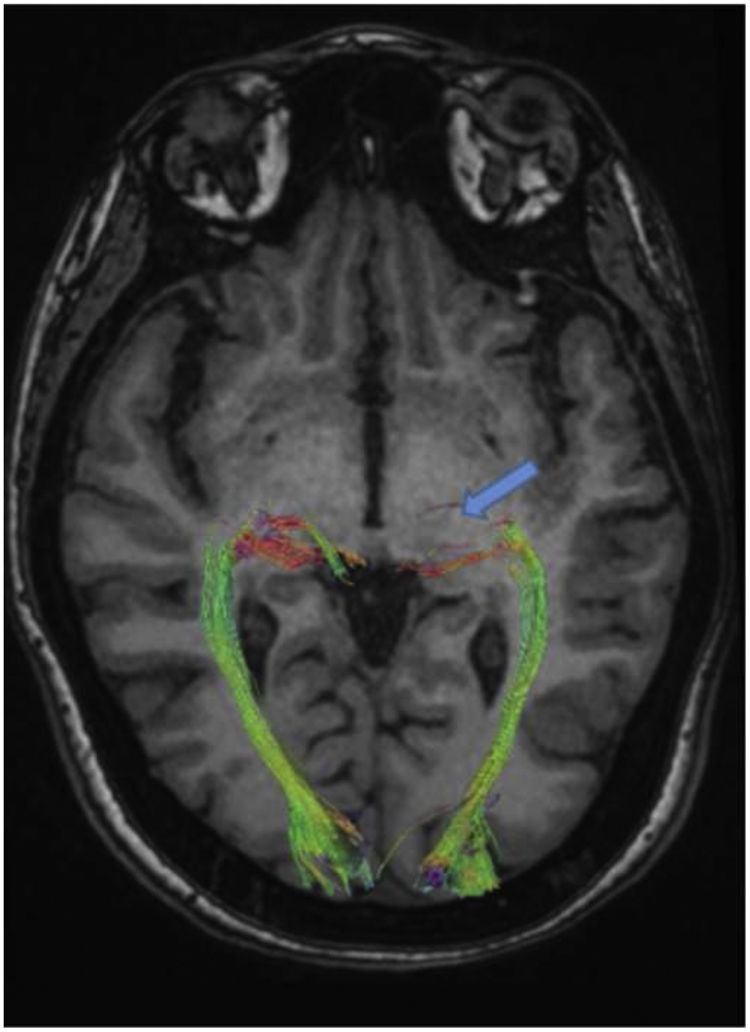

The results of DTI showed that the density of the optic radiation tract was significantly reduced. In addition, in the suspected lesion region in the left dorsolateral pons, the MD map showed increased diffusivity. Furthermore, FA and tract diameter showed significant alterations in the radiation of the patient's left optic nerve (Fig. 2). Moreover, the FA was decreased in areas of suspected lesions in the left dorsolateral pons. The AD and RD in suspected lesions areas of the left dorsolateral pons were increased by 67.71% and 117.65%, respectively, when compared to normal values (Fig. 3), DTI metrics in the suspected lesion areas on pons are shown in Table 1.

The quantitative DTI results based on the MD map revealed the increased diffusivity in the left optic radiation area. At the same time, the FA map demonstrated that FA is decreased in the related white matter (Table 2).

Diffusion tensor imaging (DTI) metrics in whole brain, right and left optic radiation.